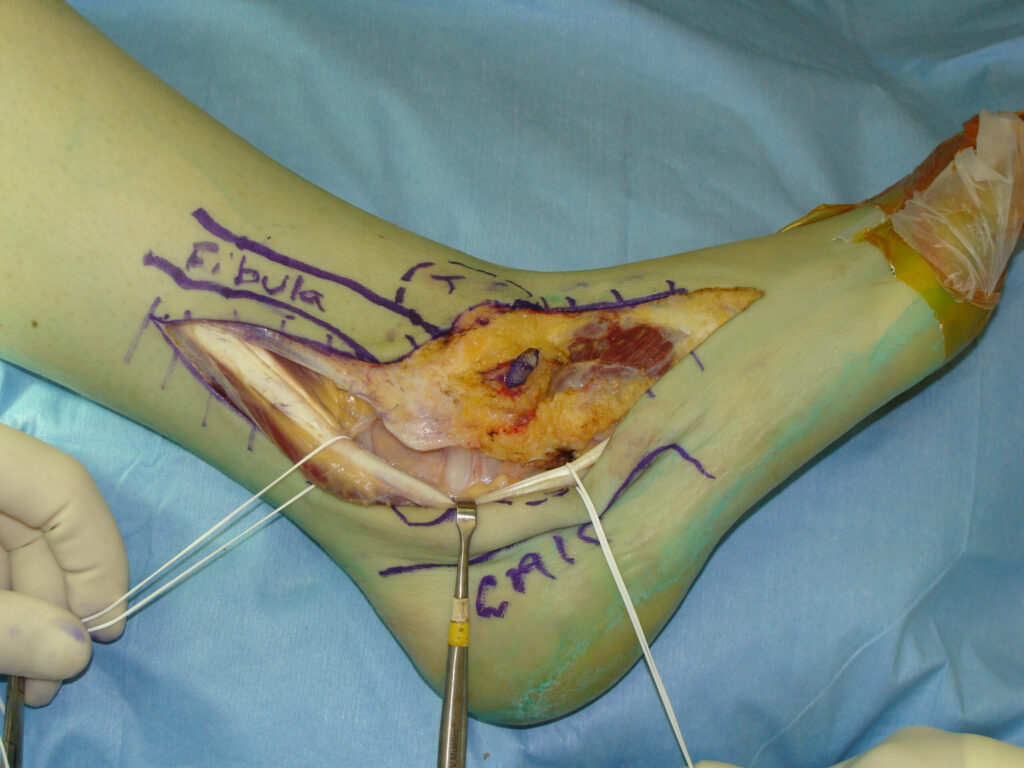

TREATMENT

Wide surgical excision is the mainstay of treatment for Synovial Sarcoma

High grade tumors:

Often requires either radical resection or wide surgical excision plus Radiotherapy

- Amputation may be required for unresectable tumors